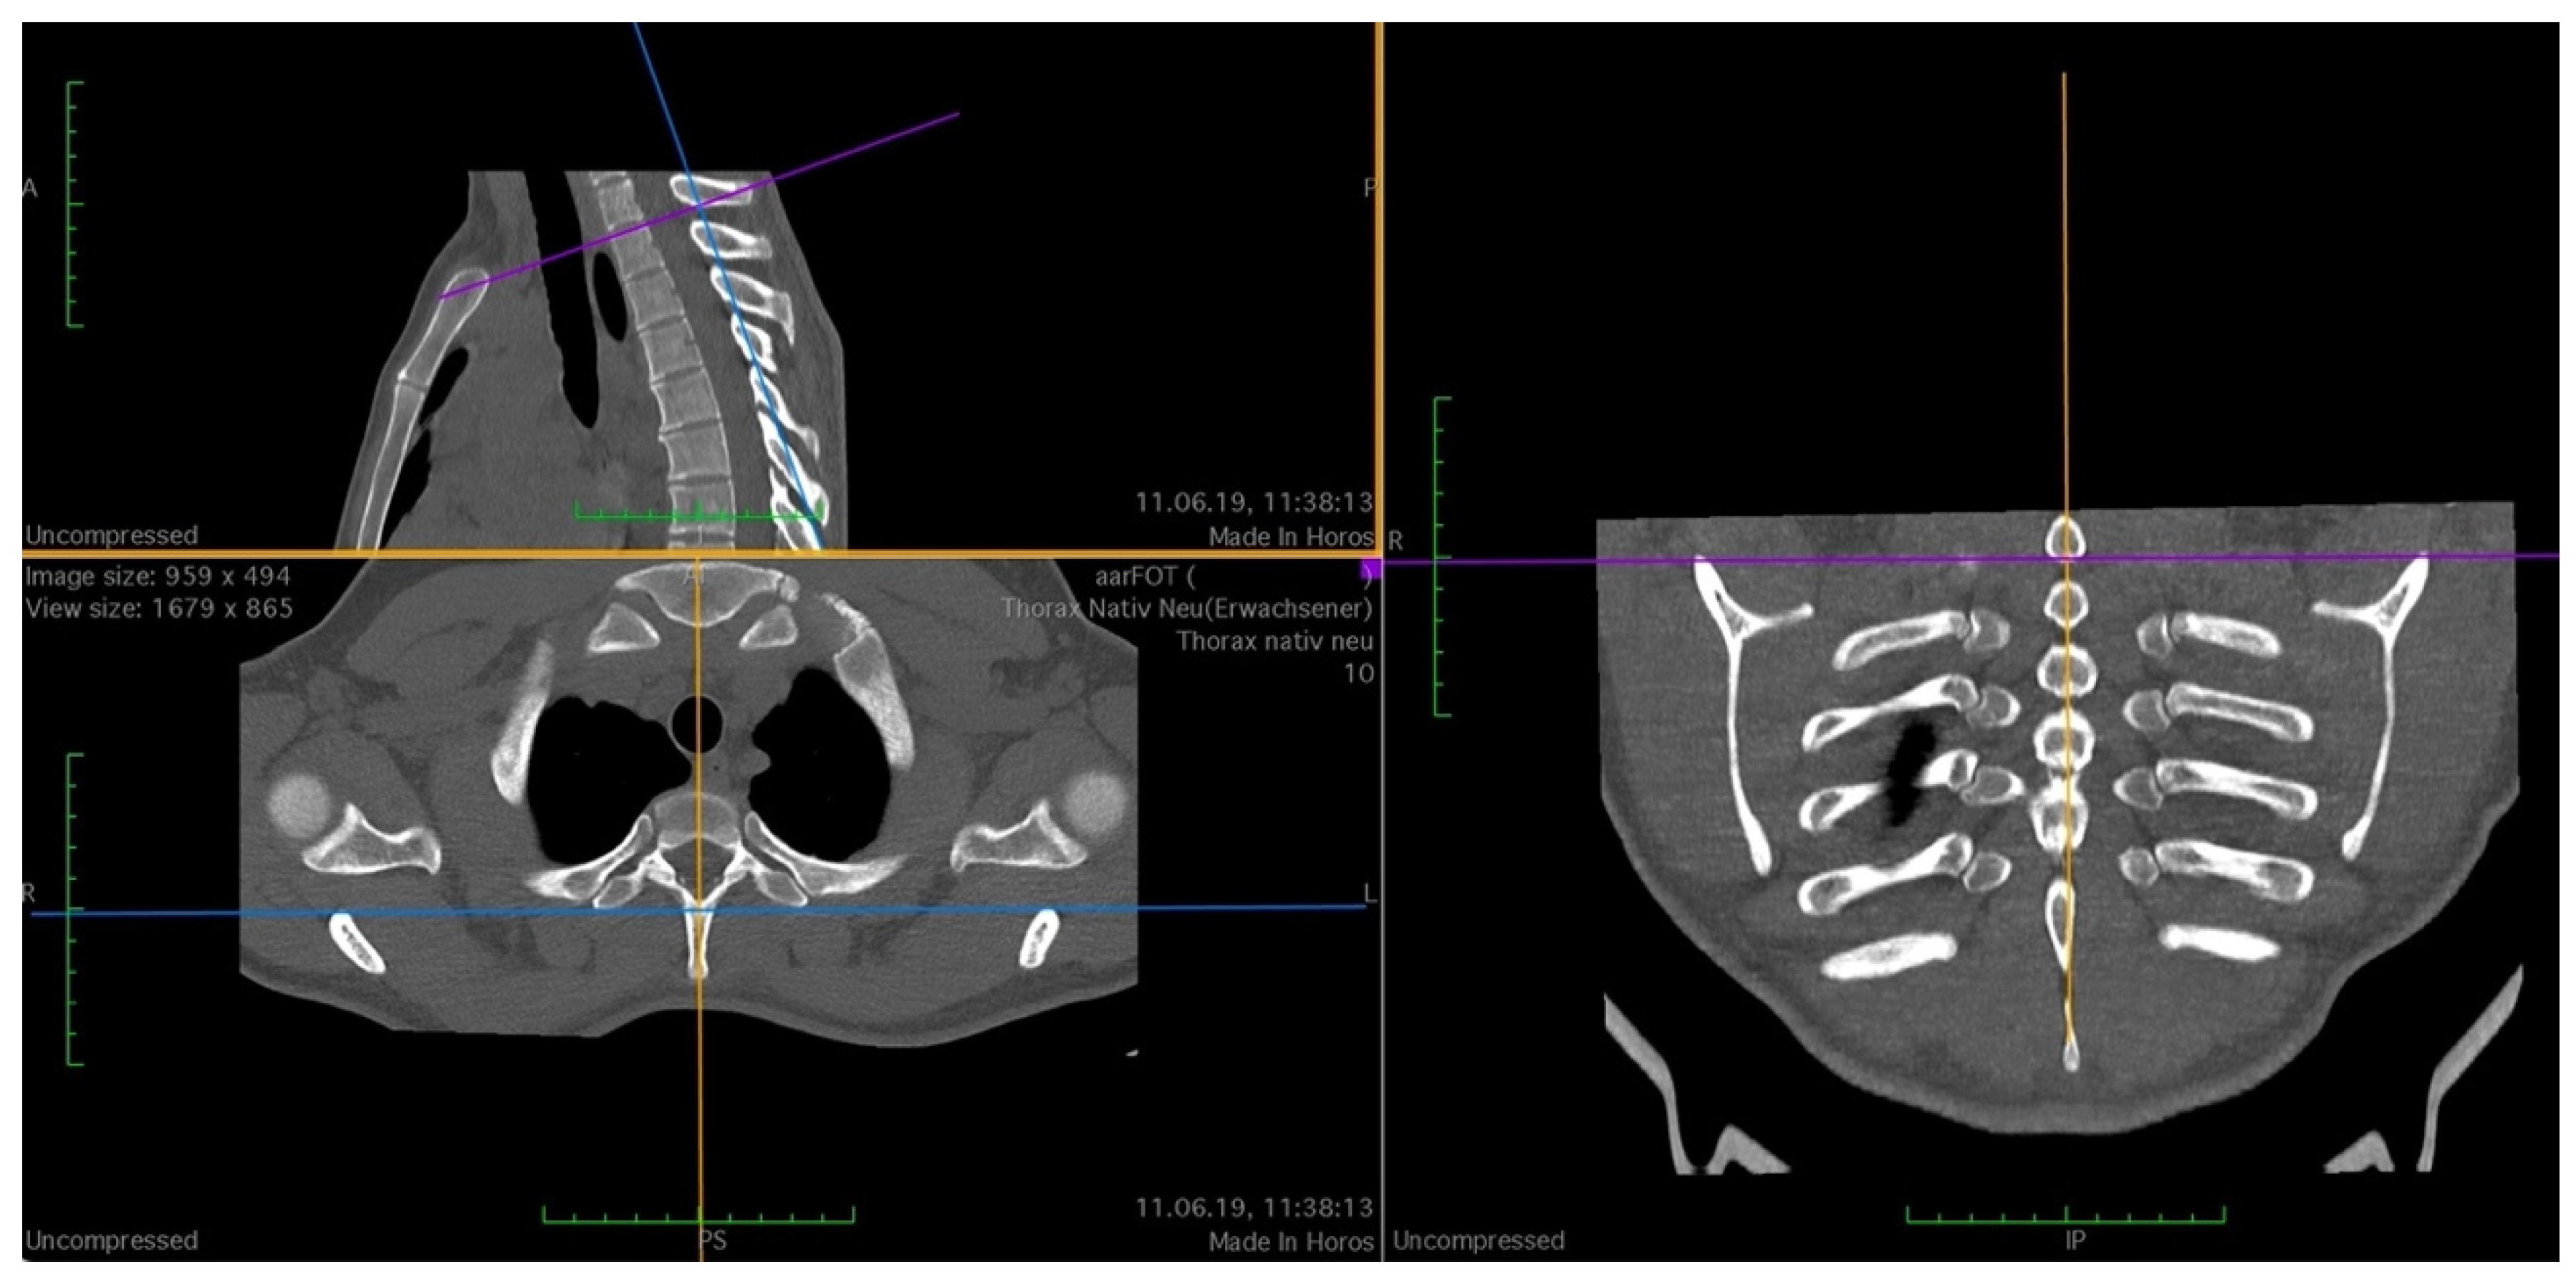

To standardize the measurements, anatomical landmarks were defined to guide the orientation of the planes and the distances to be measured. As shown in Figure 1, the sagittal plane was aligned with the processus (procc.) spinosi of the thoracic spine, and the frontal plane was tangent to the processus transversi of the first thoracic vertebra. The horizontal plane was oriented as an axis of intersection through the two joints of the first rib or at the base plate of the first thoracic vertebral body, depending on the measurement point to be examined.

Figure 1.

Setting the cutting planes in 3D MPR, purple line: horizontal plane at base plate of first thoracic vertebral body; yellow line: sagittal plane, aligned with the procc. spinosi of the thoracic spine; blue line: frontal plane, tangent to the processus transversi of the first thoracic vertebra.